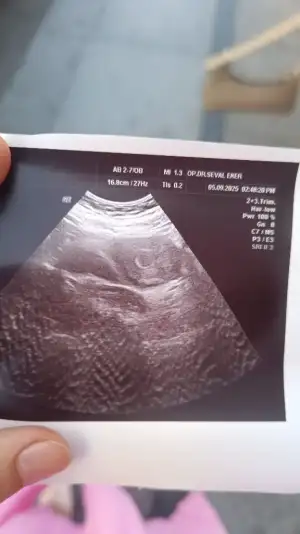

Kızlar 28 temmuz son adet tarihim 28 Ağustos da adet olmam lazımdı olmadım 1 Eylül pazartesi kan verdim (Beta HCG)sağlık ocağında 2 Eylül sonucum çıktı sonuç 2060 bu tarihlere göre betam yüksek değil mi acaba ikiz gebelik mi veyahut da normal mi Beta beni bilgilendirir misiniz